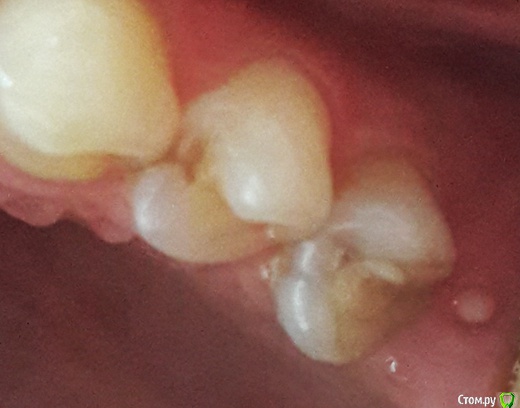

венди Опубликовано 27 февраля, 2017 Автор Поделиться Опубликовано 27 февраля, 2017 (изменено) Добрый день! Наверное, мой вопрос сейчас больше для раздела Хирургии. Но не знаю создавать ли новую тему, поэтому пишу здесь. Если нужно - перенесу. Напомню, что перед Новым годом был выкручен ФДМ, т.к. не проходило какое-то воспаление и очень сильный дискомфорт. Десна после выкручивания постепенно затянулась. Оставалось малюсенькое отверстие - через него хирург засовывал что-то острое и проверял имплант месяц назад, когда я ходила на осмотр. Пару дней назад появилась болезненность, когда кушала на левую сторону именно в области десны, где имплант. А на выходных образовался какой-то прыщик. Фото прилагаю.Сегодня ватной палочкой, смоченной в хлоргексидине его потрогала - выделилась капелька жёлтого цвета и он сильно сдулся. Что это может быть? Слизистая так выросла? Изменено 27 февраля, 2017 пользователем венди Ссылка на комментарий